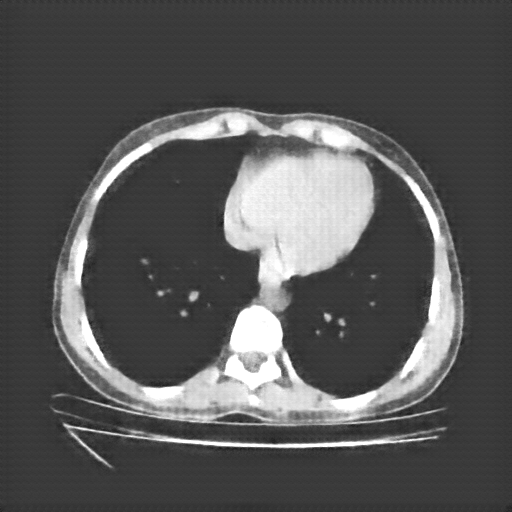

Slice 70 Targeting Evaluation

Slice: Slice_70

Conversion: NATIVE β†’ VENOUS

Image Grid

4Γ—3 grid: Rows show different image types (Original NATIVE, Reconstructed NATIVE, Original VENOUS, Generated VENOUS), Columns show windowing techniques (No Window, Lung Window, Mediastinum Window)

Reconstructed NATIVE CT scan (cycle consistency)

No window - Raw intensity values